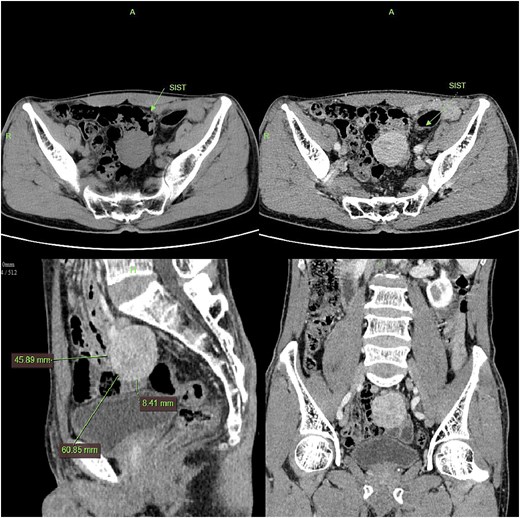

Contrast-enhanced CT demonstrated a well-circumscribed, round enhancing mass measuring 4 cm in diameter. Sagittal imaging showed the lesion positioned 0.9 cm from the bladder wall, 4.5 cm from the anterior abdominal wall, and 6.1 cm from the pubic symphysis (Fig. 2). The mass exhibited an intact capsule without evidence of rupture. MRI performed within a 24-hour period, sagittal imaging showed the lesion positioned 7.9 cm from the bladder wall, 1.3 cm from the anterior abdominal wall, and 9.3 cm from the pubic symphysis, and confirmed stable positioning and morphology, maintaining identical spatial relationships to adjacent structures (Fig. 3).

MRI demonstrates superior displacement of the tumor compared to CT, with isointense signal on T2-weighted fat-suppressed sequences, post-contrast enhancement, and hyperintensity on DWI at a b-value of 800 s/mm².

SISTs typically follow an insidious and asymptomatic course, frequently discovered incidentally during imaging performed for unrelated indications. Preoperative diagnosis relies primarily on imaging, with relatively high diagnostic yield for larger tumors. In this case, the tumor was an incidental finding during a bladder-oriented examination. It did not cause significant bladder compression or associated symptoms, such as urinary frequency. CT provided detailed multiplanar information, revealing a pelvic mass surrounded by abundant bowel loops. Following contrast CT, the tumor exhibited significant and relatively homogeneous enhancement without calcification; these features are typical for GISTs [3]. The absence of bowel preparation, combined with intraluminal gas and indistinct perilesional omental fat, complicates differentiation from entities such as small intestinal lymphoma. MRI demonstrated anterior and superior displacement of the mass relative to its position on CT. On T1-weighted images, the lesion demonstrated low to intermediate signal intensity (SI), while T2-weighted images revealed heterogeneous SI. Fat-saturated sequences showed no evidence of low signal intensity. Diffusion-weighted imaging (DWI) and apparent diffusion coefficient (ADC) mapping confirmed the solid nature and high cellularity of the mass, characteristic features of abdominal mesenchymal tumors. Further evaluation indicated the tumor arose from the muscularis propria of an adjacent bowel loop, with a tendency to displace rather than invade surrounding structures.